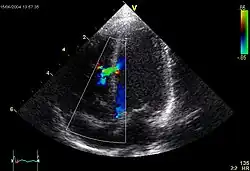

Ventricular septal defect (VSD)

Makro: Loch im Kammerseptum, meist im membranösen Teil.

Folge: Links-rechts-Shunt

Echokardiogramm eines VSD.